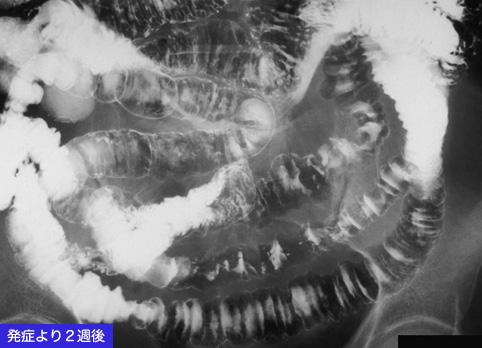

A case of an ischemic lesion due to vasculitis polymyalgia rheumatica.

[ Image ID:9861 ]

Inflammatory or ulcerative disease / lesions/Ischemic colitis

Location

Small intestine/Jejunum

Technique, Method

X-ray

40 -